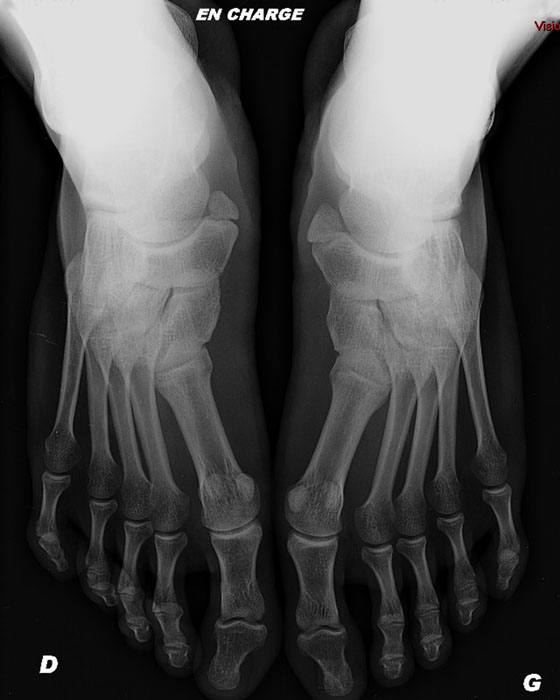

Abstract. Accessory ossicles of the foot are commonly mistaken for fractures. The accessory navicular is one of the most common accessory ossicles of the foot. There is a higher incidence in women and the finding might be bilateral in 50-90%. This entity is usually asymptomatic, although populations with medial foot pain have a higher prevalence.. Classification. The Geist classification divides the accessory navicular bones into three types. Type 1: An os tibiale externum is a 2-3 mm sesamoid bone in the distal posterior tibialis tendon.Usually asymptomatic. Type 2: Triangular or heart-shaped ossicle measuring up to 12 mm, which represents a secondary ossification center connected to the navicular tuberosity by a 1-2 mm layer of.

The accessory navicular bone is one of several accessory ossicles of the foot and is considered as a normal anatomic and radiographic variant (1-10).Accessory navicular bones are classified into three types based on their shape and location in relation to the navicular bone (3-6).Type I is a 2-3 mm sized sesamoid bone in the posterior tibial tendon (PTT) and is referred to as "os tibiale.. The Geist1 classification divides accessory navicular bones into three types: type 1 accessory navicular bone. also known as os tibiale externum. 2-3 mm sesamoid bone embedded within the distal portion of the posterior tibial tendon. no cartilaginous connection to the naviculam tuberosity and may be separated from it by up to 5 mm.